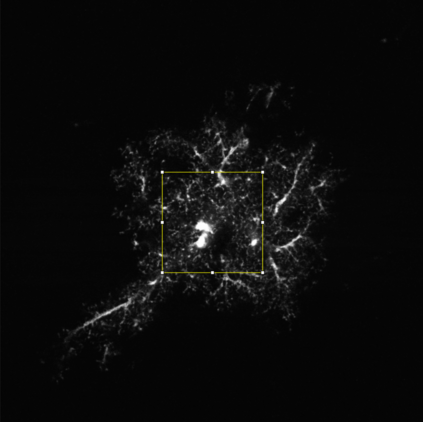

The quality of microscopy images often suffers from optical aberrations. These aberrations and their associated point spread functions have to be quantitatively estimated to restore aberrated images. The recent state-of-the-art method PhaseNet, based on a convolutional neural network, can quantify aberrations accurately but is limited to images of point light sources, e.g. fluorescent beads. In this research, we describe an extension of PhaseNet enabling its use on 3D images of biological samples. To this end, our method incorporates object-specific information into the simulated images used for training the network. Further, we add a Python-based restoration of images via Richardson-Lucy deconvolution. We demonstrate that the deconvolution with the predicted PSF can not only remove the simulated aberrations but also improve the quality of the real raw microscopic images with unknown residual PSF. We provide code for fast and convenient prediction and correction of aberrations.